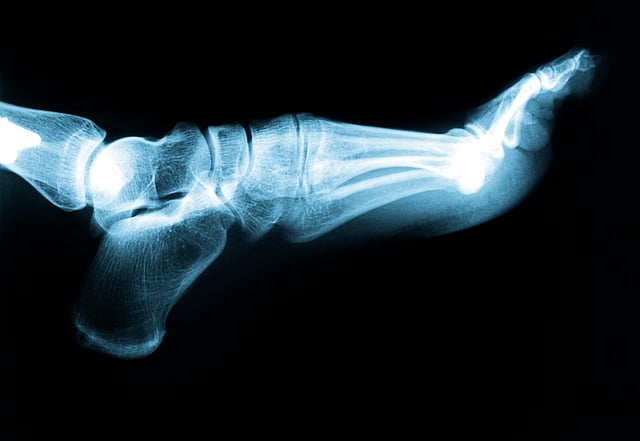

It is estimated that up to 50 per cent of people with diabetes will develop damage to peripheral nerves during their lifetime, and up to 50 per cent will experience pain because of that nerve damage. iStock

It has been estimated that up to 50 per cent of people with diabetes will develop damage to peripheral nerves during their lifetime, and up to 50 per cent will experience pain because of that nerve damage.